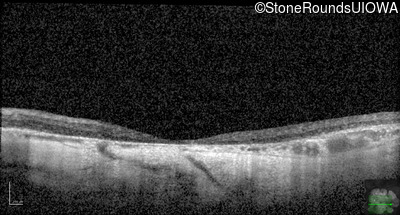

Age at visit: 43 years

OD OS